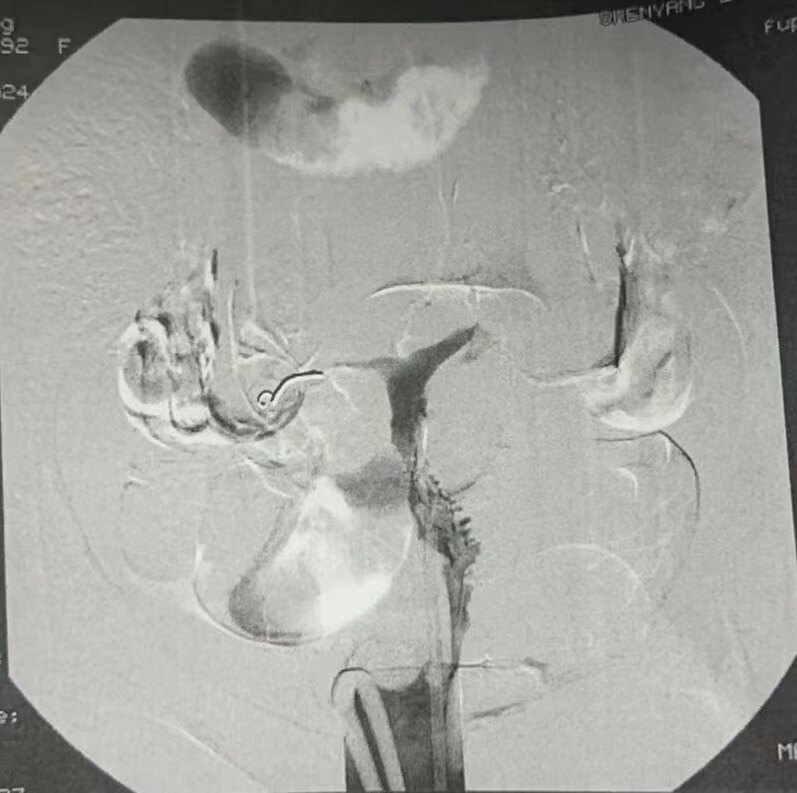

典型的双侧输卵管造影图

此病例造影双侧输卵管没有积水

栓塞后片(相当于延迟弥散相片)双侧输卵管也没有积水征象